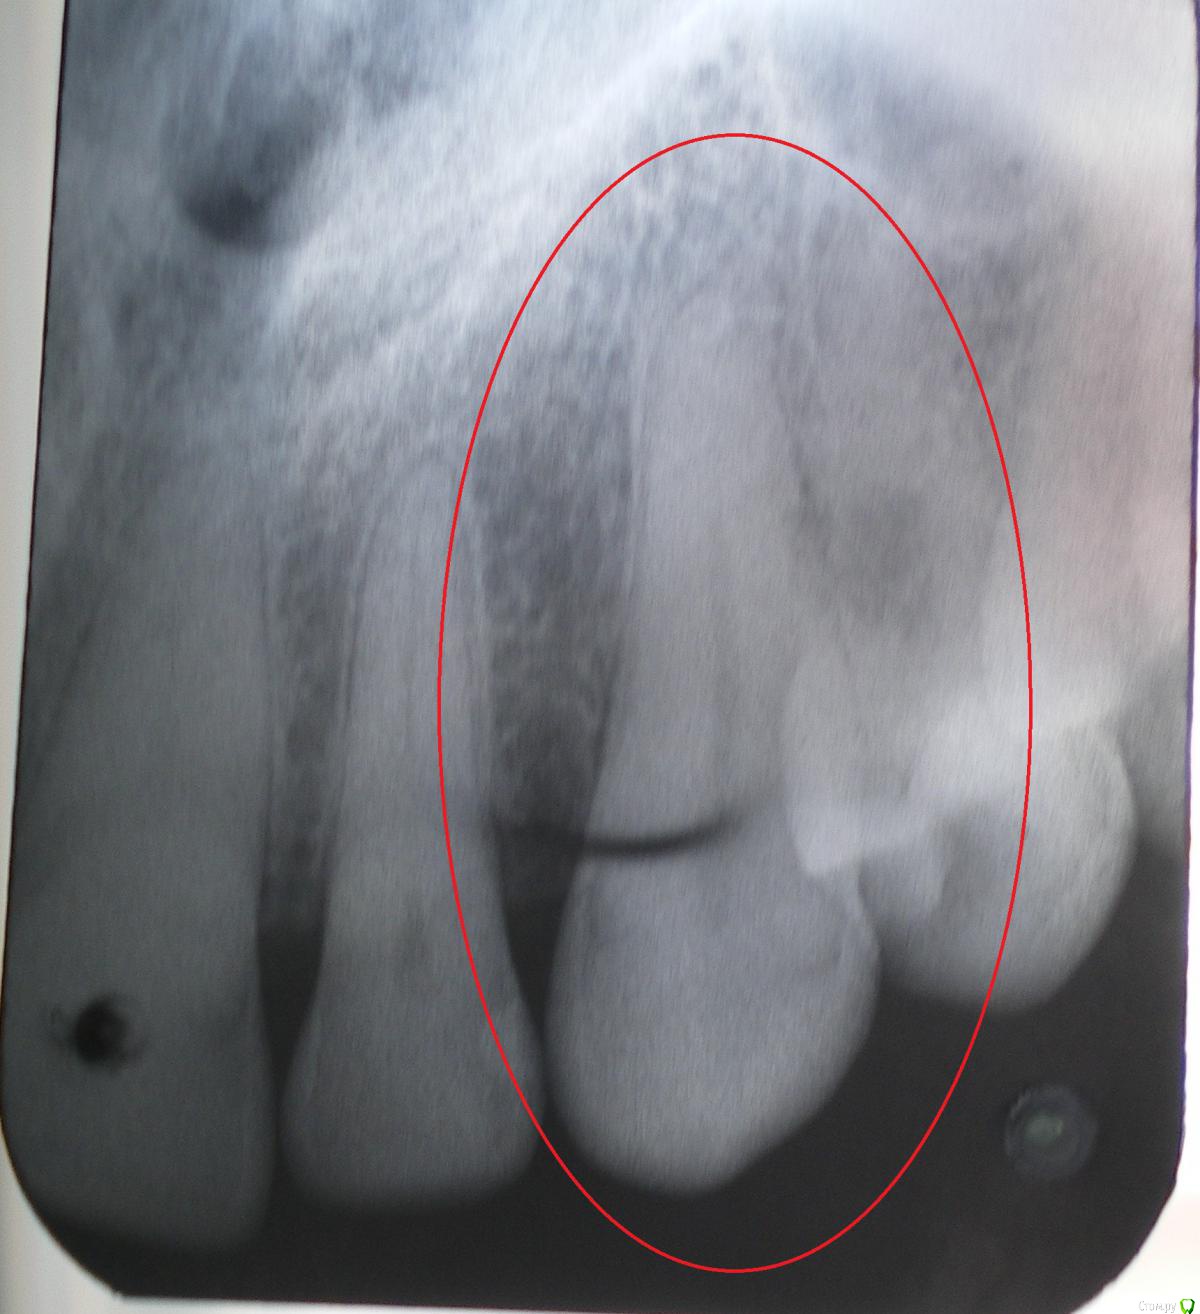

ganofer Опубликовано 21 мая, 2020 Поделиться Опубликовано 21 мая, 2020 Здравствуйте,подскажите по снимку, пожалуйста, не совсем понятно:на снимке (зуб выделен красной чертой) кариозная полость или зуб здоров?Спасибо. Ссылка на комментарий

red_butler Опубликовано 21 мая, 2020 Поделиться Опубликовано 21 мая, 2020 качество снимков не позволяет дать ответ Ссылка на комментарий